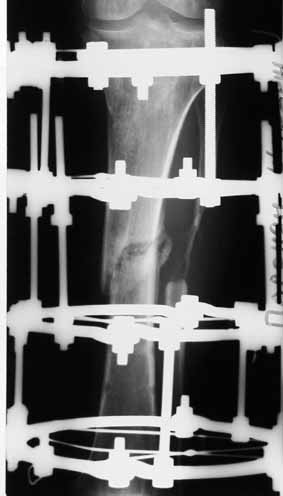

1 июня произведено удаление гвоздя, дренаж костномозгового канала, остеосинтез аппаратом Илизарова ( after 1; 2).

Ввиду относительной тугоподвижности ложного сустава и наличия признаков репаративной активности костной ткани рентгенологически, после 10 дней компрессии на стыке отломков, начали дистракцию по 1мм в день. Выписан на амбулаторное лечение. Отделяемое в нижней трети голени прекратилось, ранка закрылась. Интраоперационно и 5 дней после операции получал ципроксациллин. В июле по передней поверхности голени в зоне регенерата открылась ранка с обильным гнойным отделяемым. После локального лечения, ранка в течении двух недель эпителизировалась и полностью закрылась. Дистракцию не прекращали. (during 1, 2)